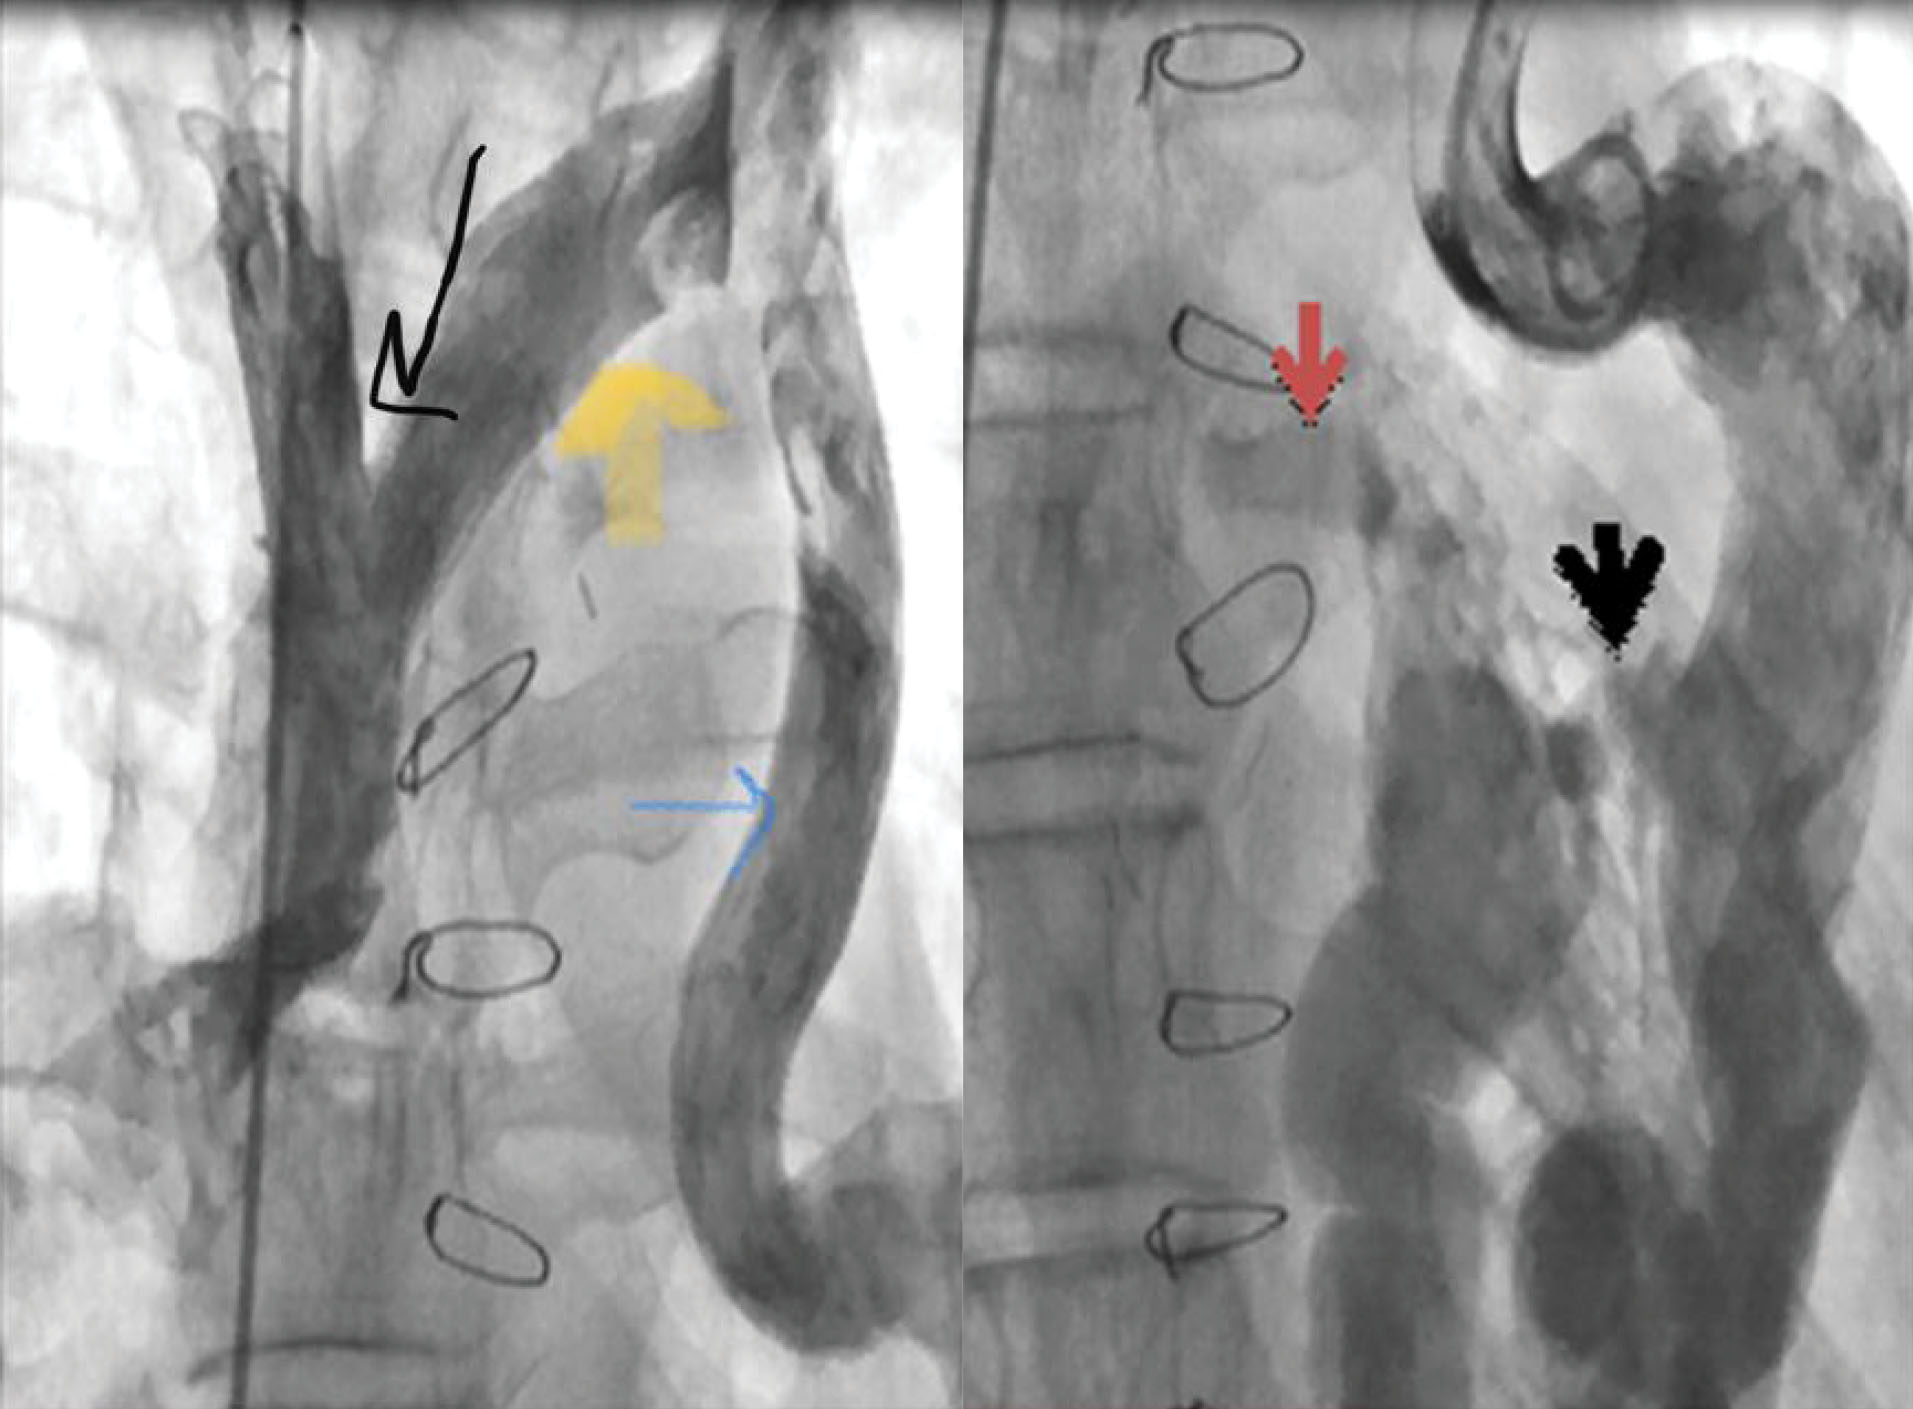

Hemoglobin concentration was 17g/dL. Electrocardiogram showed low voltage, poor R progression and left anterior hemiblock. Contrast trans-thoracic echocardiography (TTE) with an injection of agitated saline from left brachial vein showed a left-sided dilated para-aortic vessel including a blue color descending flow suggested left superior vena cava (LSVC) with a fast entrance of bubbles into the left atrium (). Finally, she underwent cardiac magnetic resonance imaging (CMR) due to cyanosis which revealed the presence of very engorged dilated left lower and left upper pulmonary veins with fistulous connection which left upper pulmonary vein (LUPV) connected to vertical vein and then into an innominate vein and finally SVC. The direction of flow was from SVC to left upper pulmonary vein, left lower pulmonary vein, and left atrium (LA). (). This Fistula was seen as collateral vessels connected proximally to the inferior aspect of innominate vein and distally to the left lower pulmonary vein. There were some connections between the ascending, and descending limbs of these tortuous venous collaterals and these direct connections between venous collateral vessels could explain fast pass of agitated saline into LA during TTE with contrast study and severe cyanosis of the patient. Probably this abnormal connection of LUPV to vertical vein (PAPVC) was not diagnosed before Fontan operation and developed gradually due to the pressure gradient in the Fontan circuit with connection to LLPV. This pressure gradient could result in further dilatation of vertical vein and prominence of collateral vessels which were connected to the inferior aspect of innominate vein. Thus, catheterization was performed () and Femoral vein was cannulated. We passed from IVC to fontan circuit, SVC, innominate and lastly vertical vein. In injection in vertical vein, we found severe engorged and tortoise pulmonary veins, then a long stiff exchange wire (260 cm) with a long LIFETECH delivery sheath 9F passed through fontan circuit to SVC, innominate vein and vertical vein. An ADO device 14*16 mm chosen and deployed at proximal of vertical vein (). After the detachment of device by vertical injection we confirmed proper position of device and small residual flow. The oxygen saturation immediately increased from 80% to 93%. In the first echocardiography performed after device closure, some contrast agents were entered into the left atrium through a right to left shunt, which indicates the presence of a residual shunt. This might be due to the delayed endothelialization of implanted device.

jcvtr-13-364-g003

Figure 3. Cardiac catheterization disclosed reflux of contrast from the vertical vein into the innominate vein and superior vena cava(A).A large feeder vessel arises from the left vertical vein with fistulous connection to the left inferior pulmonary vein which drained into left atrium (red arrow). A plexus of veins arising from the descending limb of fistulous connection and drained immediately into ascending limb of Venous fistula (thick black arrow)(B).